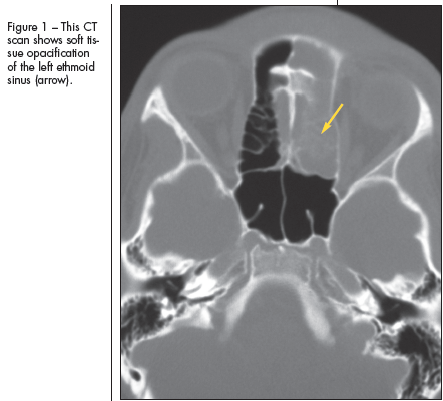

Pott puffy tumor was originally described by Sir Percivall Pott in 1768. In most patients, the process begins with frontal or ethmoid sinusitis (Figure 1) that deteriorates into an associated subgaleal abscess and frontal osteomyelitis (Figure 2). Complications include epidural or subdural abscesses (Figure 3), meningitis, and encephalitis. Periorbital abscesses and cellulitis may also represent complications of worsening sinusitis.